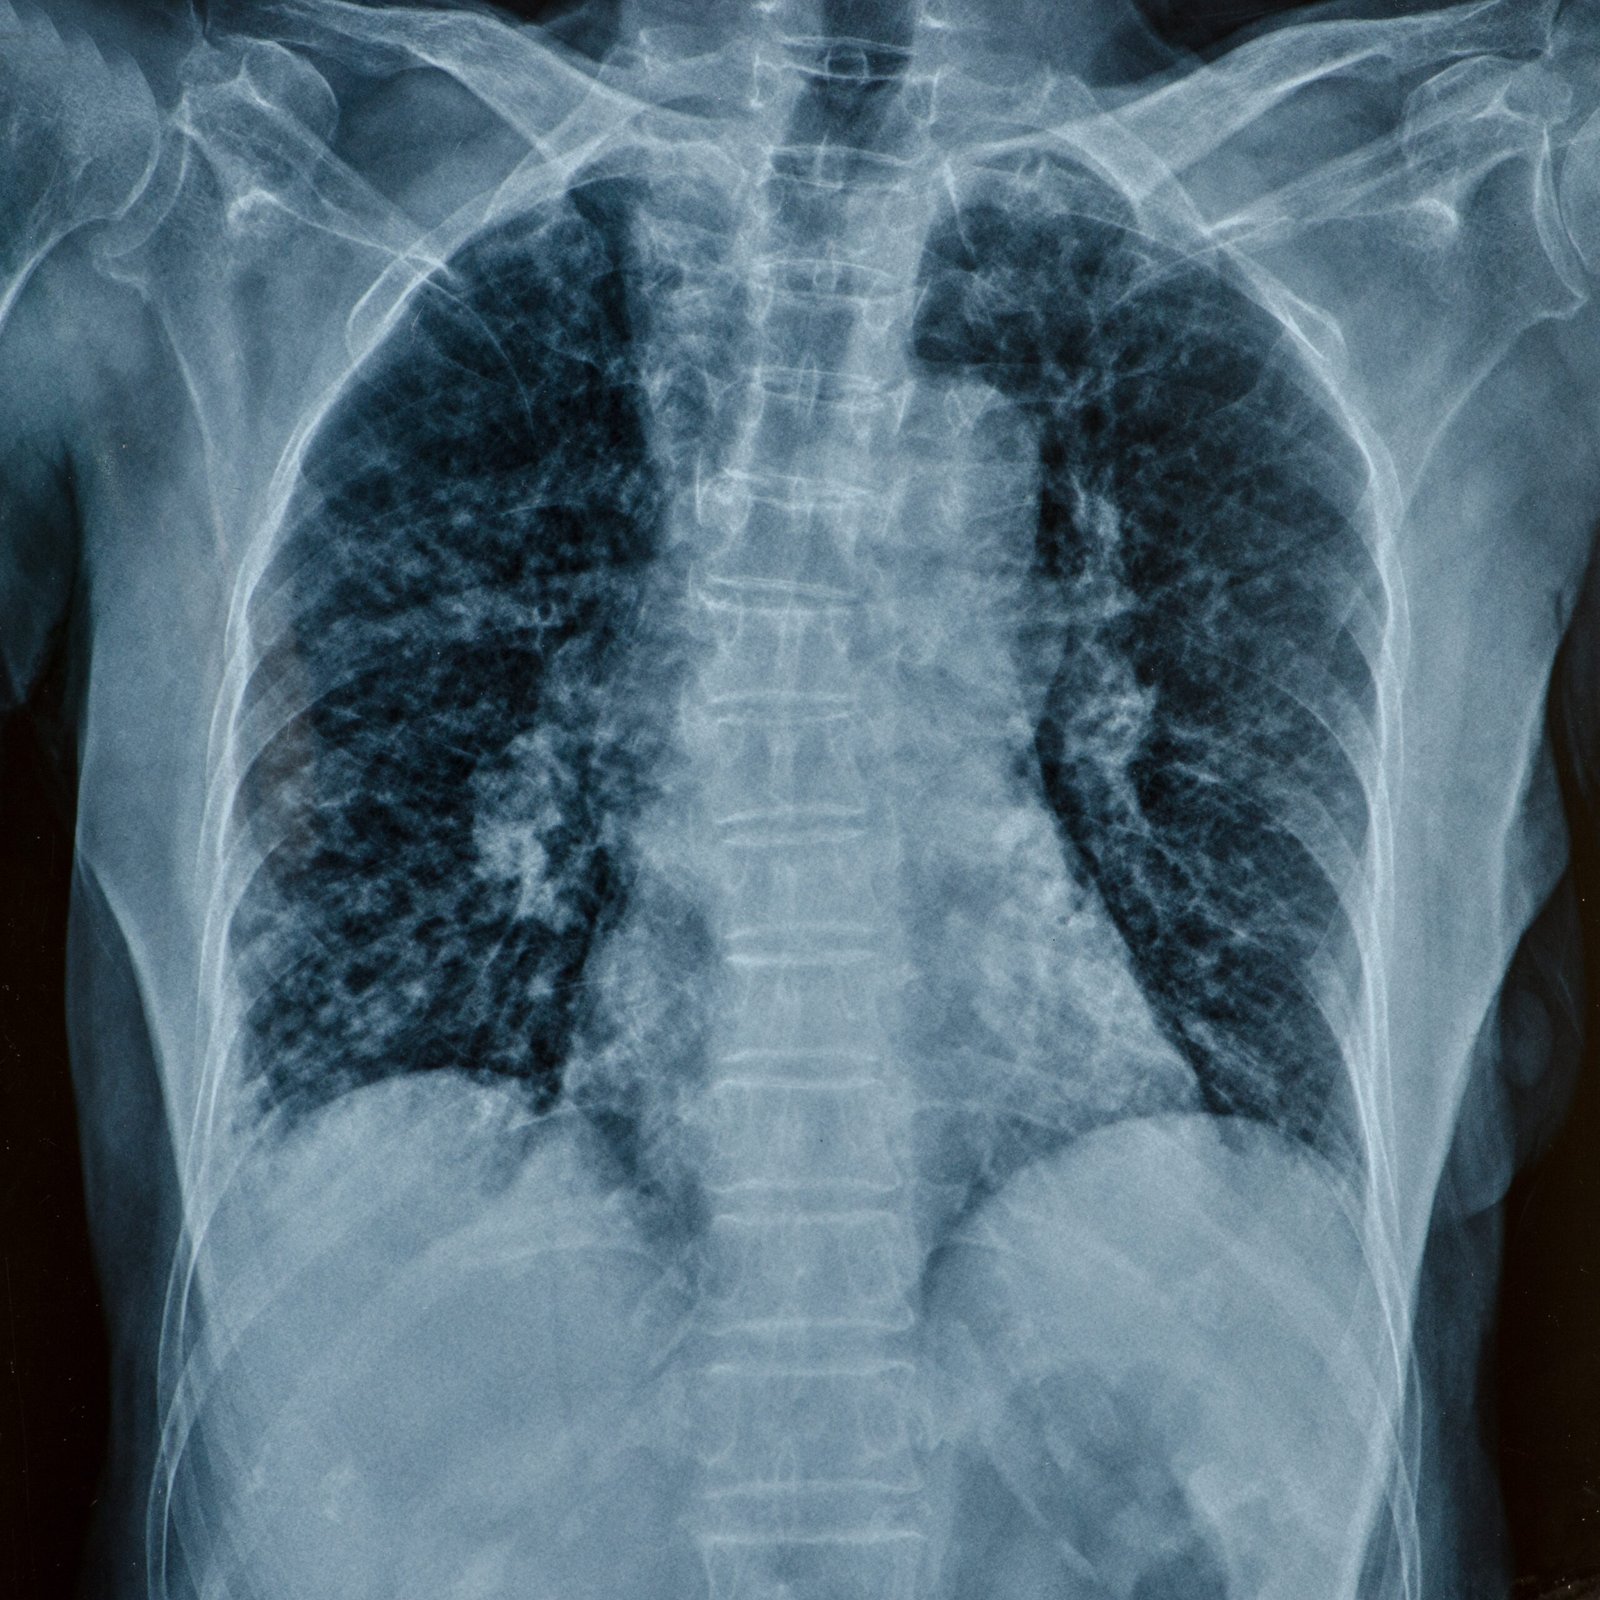

La rentrée scolaire approche, et la radiologie pédiatrique est cruciale pour le bien-être des enfants. Elle permet de détecter des anomalies grâce à des examens ciblés. Cela aide à prévenir les problèmes de développement.

La radiologie surveille aussi la croissance des os et des articulations. C’est vital pour ajuster les traitements. Elle aide à suivre la santé de chaque enfant de près.

- Radiographie du thorax pour les poumons et le cœur

| Examen radiologique | Durée moyenne | Fréquence recommandée |

|---|---|---|

| Radiographie du thorax | 5 à 10 minutes | 1 fois par an |

| Échographie abdominale | 15 à 20 minutes | Selon les besoins |

| IRM cérébrale | 30 à 45 minutes | Selon les indications médicales |

En tant que professionnels, nous savons que la radiologie pédiatrique est essentielle. Elle aide les enfants à grandir sains et à réussir.